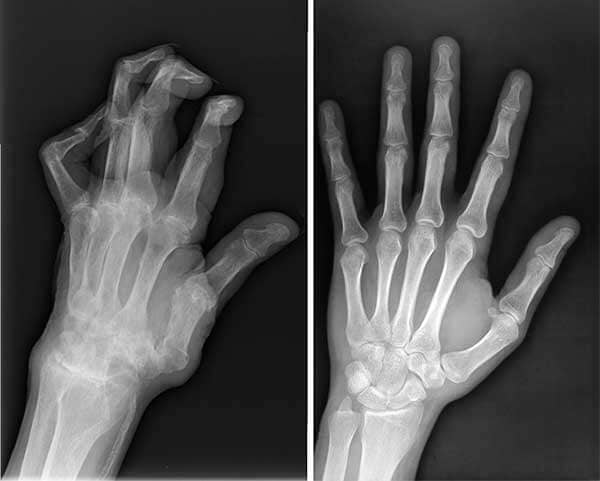

Manos antes y después

Radiografías de las manos de mi esposo antes y después de Ostex.